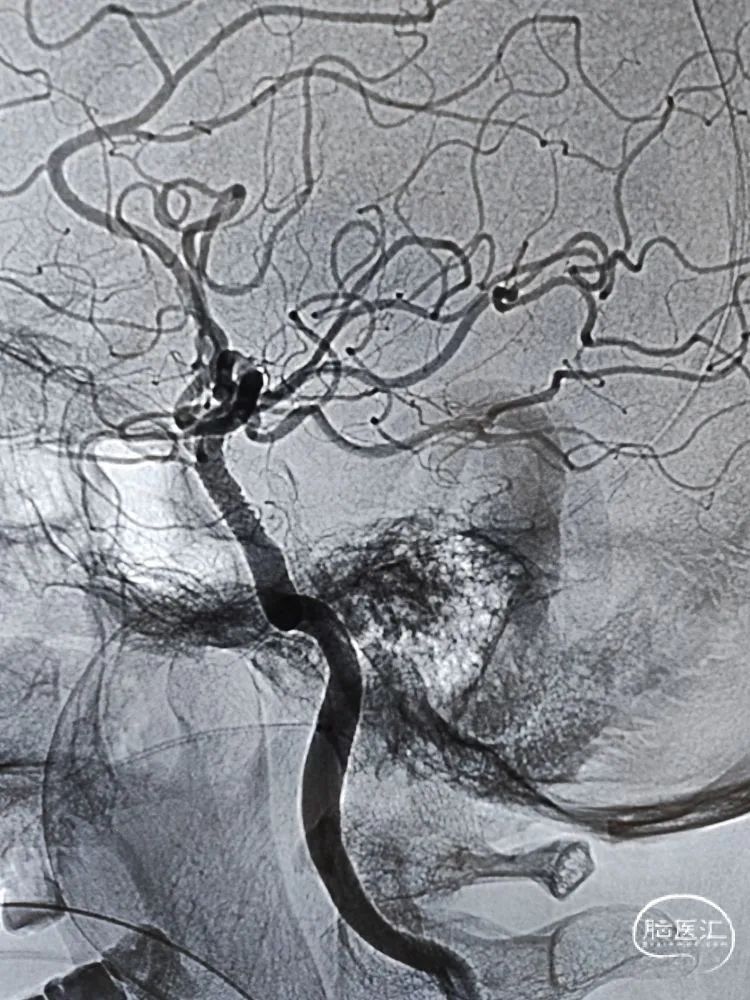

留置微导丝,撤出支架释放系统,观察10分钟后造影提示血流无异常,遂撤出微导丝。侧位、正位造影减影像和非减影像提示颈内动脉海绵窦段支架内和远端血流通畅,支架顺应血管贴壁良好;由于近端血流改善,后交通动脉充分显影。